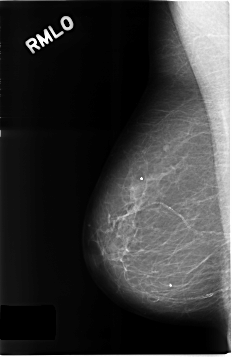

C_0303_1.RIGHT_MLO

RIGHT_MLO LINES 4632 PIXELS_PER_LINE 3008 BITS_PER_PIXEL 12 RESOLUTION 50 NON_OVERLAY